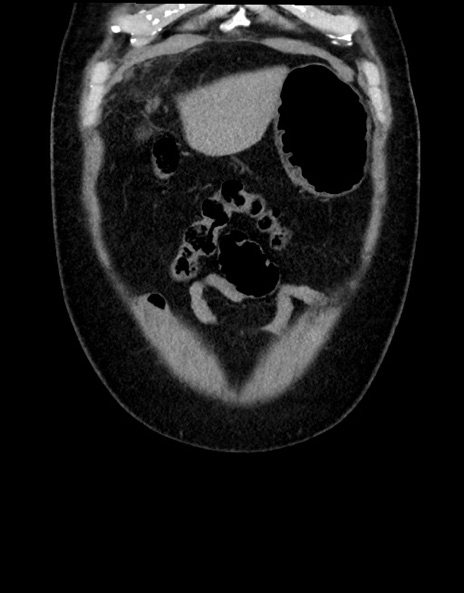

横断像